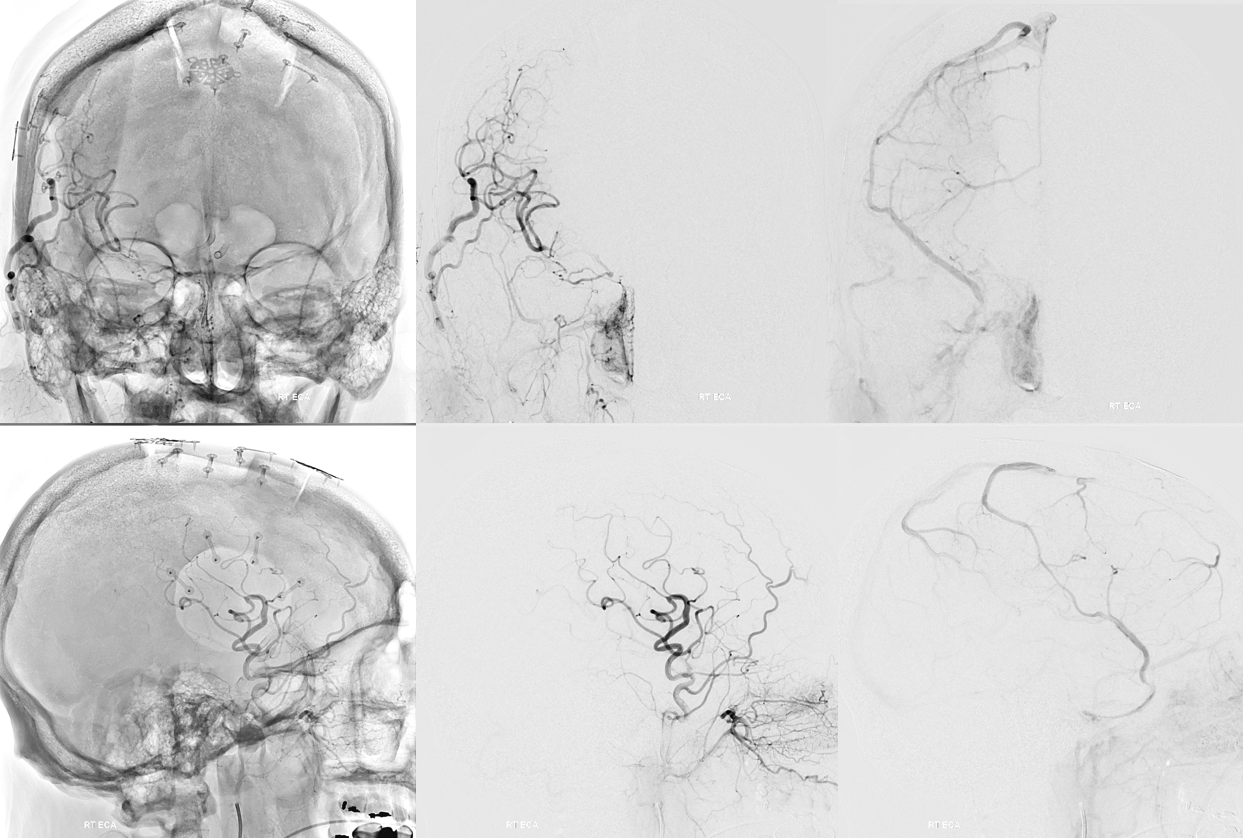

Now to the left side

Two Pipe Shields are placed. This is how we work. This big one is not a job for one and done

Post. Bilateral injections. The right ACA is supplied retrogradely via the ACA-ACA bypass. The MOST important finding here is that there is no longer flow across the ACOM. This is what flow modification is. Changing dynamics to impact aneurysm.

Robust bypass supports superior division and some more

No aneurysm, as suspected

Stereo pairs

Bypasses. Note A3-A3 patent bypass, as well as STA-MCA. Both seen thru radiolucent skull windows